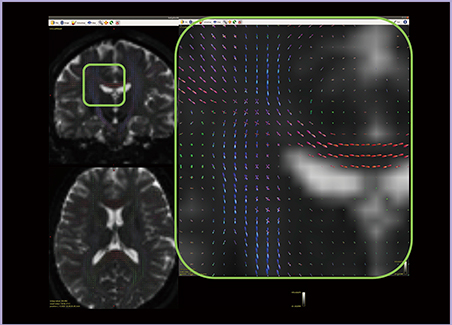

舌痛症14例と,年齢・性別をマッチしたコントロール11例を対象にTBSSを用いて解析したところ,非常に広範にMDの変化が確認された。使用している表示ツールFSLeyesには複数のアトラス機能が実装されており,当該ボクセルが存在する部位の情報を得ることができる。同じ症例群でFAを解析すると両群で有意差が認められる部分があり,JHU White-Matter Tractography Atlasを使用して位置を確認した(図1)。有意差がある部分(赤)は,M1(紫)やS1(水色),M1とS1の混在部分(緑)に近接し,比較的感覚路に近い部分に群間差が見られることがわかった。MDでもM1近傍に加え,M1+S1やS1の部分を含む広範な部位に群間差が確認された。一方,ADでは群間差が見られず,RDではMDと同様の群間差が認められており,感覚路に関連した異常が存在すると考えられる。

図1 TBSSを用いたDTI解析結果(FA)